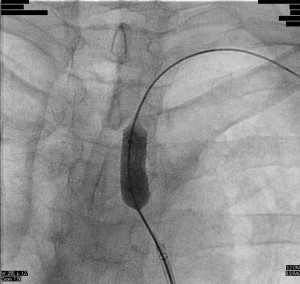

A 6F 65 cm sheath was advanced to the left subclavian artery and a 7 mm diameter 40 mm length balloon was positioned at the lesion over a 0.035 inch J-tip wire. The balloon was inflated to 8 atmospheres for thirty seconds:

At this point, the balloon would not deflate and could not be retracted into the sheath. Attempts to aspirate and dilute the contrast in the balloon were unsuccessful. Though a wire was passed around the balloon, it could not be snared. After some deliberation, it was decided to pull the balloon back to the brachial artery (Figure 3):